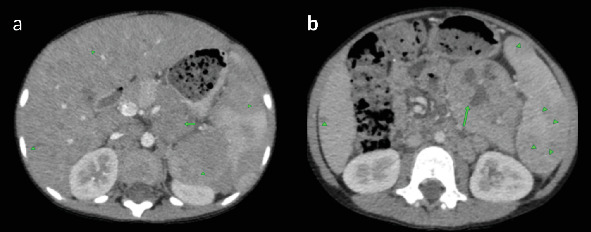

t细胞/组织细胞丰富的大b细胞淋巴瘤(THRLBCL)是弥漫性大b细胞淋巴瘤(DLBCL)的一种罕见的侵袭性亚型,在儿童中并不常见。在这里,我们提出一个8岁的男性病例,他有3个月的低度间歇性发热史,体重明显减轻,食欲不振,腹部肿胀。检查显示脾肿大,腹部中部可触及肿块,实验室结果显示双氧体减少。影像学显示肝脾肿大,弥漫性低密度肝脏和脾脏病变,肠系膜和腹膜后淋巴结病变。肠系膜肿块的核心穿刺活检证实了诊断,组织病理学显示分散的大单核和双核细胞,背景是小淋巴细胞和组织细胞。免疫组织化学显示CD45、CD20和EMA呈阳性,CD30、CD15和Bcl-2呈阴性,排除了其他诊断,如结节性淋巴细胞显性霍奇金淋巴瘤(NLPHL)和经典霍奇金淋巴瘤(cHL)。患者最初通过环磷酰胺、长春新碱和泼尼松(COP)的前期方案稳定,随后用R-COPADM(利妥昔单抗、环磷酰胺、长春新碱、泼尼松和甲氨蝶呤)诱导和巩固。治疗后影像学显示淋巴结病变和肝脾肿大明显消退,无残留或复发疾病。在随访中,患者仍处于临床缓解期,无进展迹象。该病例强调了早期识别,详细的组织病理学评估以及免疫组织化学在准确诊断儿童THRLBCL中的作用,确保及时开始有效治疗并改善这种罕见的儿科恶性肿瘤的预后。

T-cell/histiocyte-rich large B-cell lymphoma (THRLBCL) is a rare and aggressive subtype of diffuse large B-cell lymphoma (DLBCL) that is uncommon in children. Here, we present the case of an 8-year-old male with a 3-month history of low-grade intermittent fever, significant weight loss, loss of appetite, and progressive abdominal swelling. Examination revealed splenomegaly and a palpable midabdominal mass, with laboratory findings showing bicytopenia. Imaging demonstrated hepatosplenomegaly, diffuse hypodense liver and spleen lesions, and mesenteric and retroperitoneal lymphadenopathy. A core-needle biopsy of the mesenteric mass confirmed the diagnosis, with histopathology revealing scattered large mononuclear and binucleate cells in a background of small lymphocytes and histiocytes. Immunohistochemistry showed positivity for CD45, CD20, and EMA and negativity for CD30, CD15, and Bcl-2, excluding alternative diagnoses such as nodular lymphocyte-predominant Hodgkin lymphoma (NLPHL) and classical Hodgkin lymphoma (cHL). The patient was initially stabilized with a prephase regimen of cyclophosphamide, vincristine, and prednisone (COP), followed by induction and consolidation with R-COPADM (rituximab, cyclophosphamide, vincristine, prednisone, and methotrexate). Posttreatment imaging revealed significant resolution of lymphadenopathy and hepatosplenomegaly, with no residual or recurrent disease. At follow-up, the patient remains in clinical remission with no signs of progression. This case highlights the importance of early recognition, detailed histopathological evaluation, and the role of immunohistochemistry in accurately diagnosing THRLBCL in children, ensuring timely initiation of effective therapy and improving outcomes in this rare pediatric malignancy.